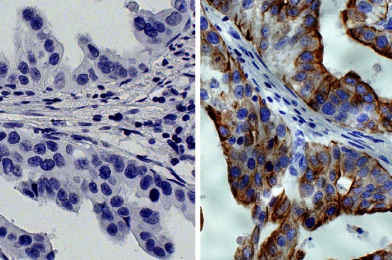

石蠟包埋的人胃癌組織用小鼠IgG2a-HRP同種型對照(SB貨號0103-05;左側(cè))和小鼠抗細(xì)胞角蛋白8-HRP(SB貨號10080-05;右側(cè))染色,隨后用DAB和蘇木精進(jìn)行染色。